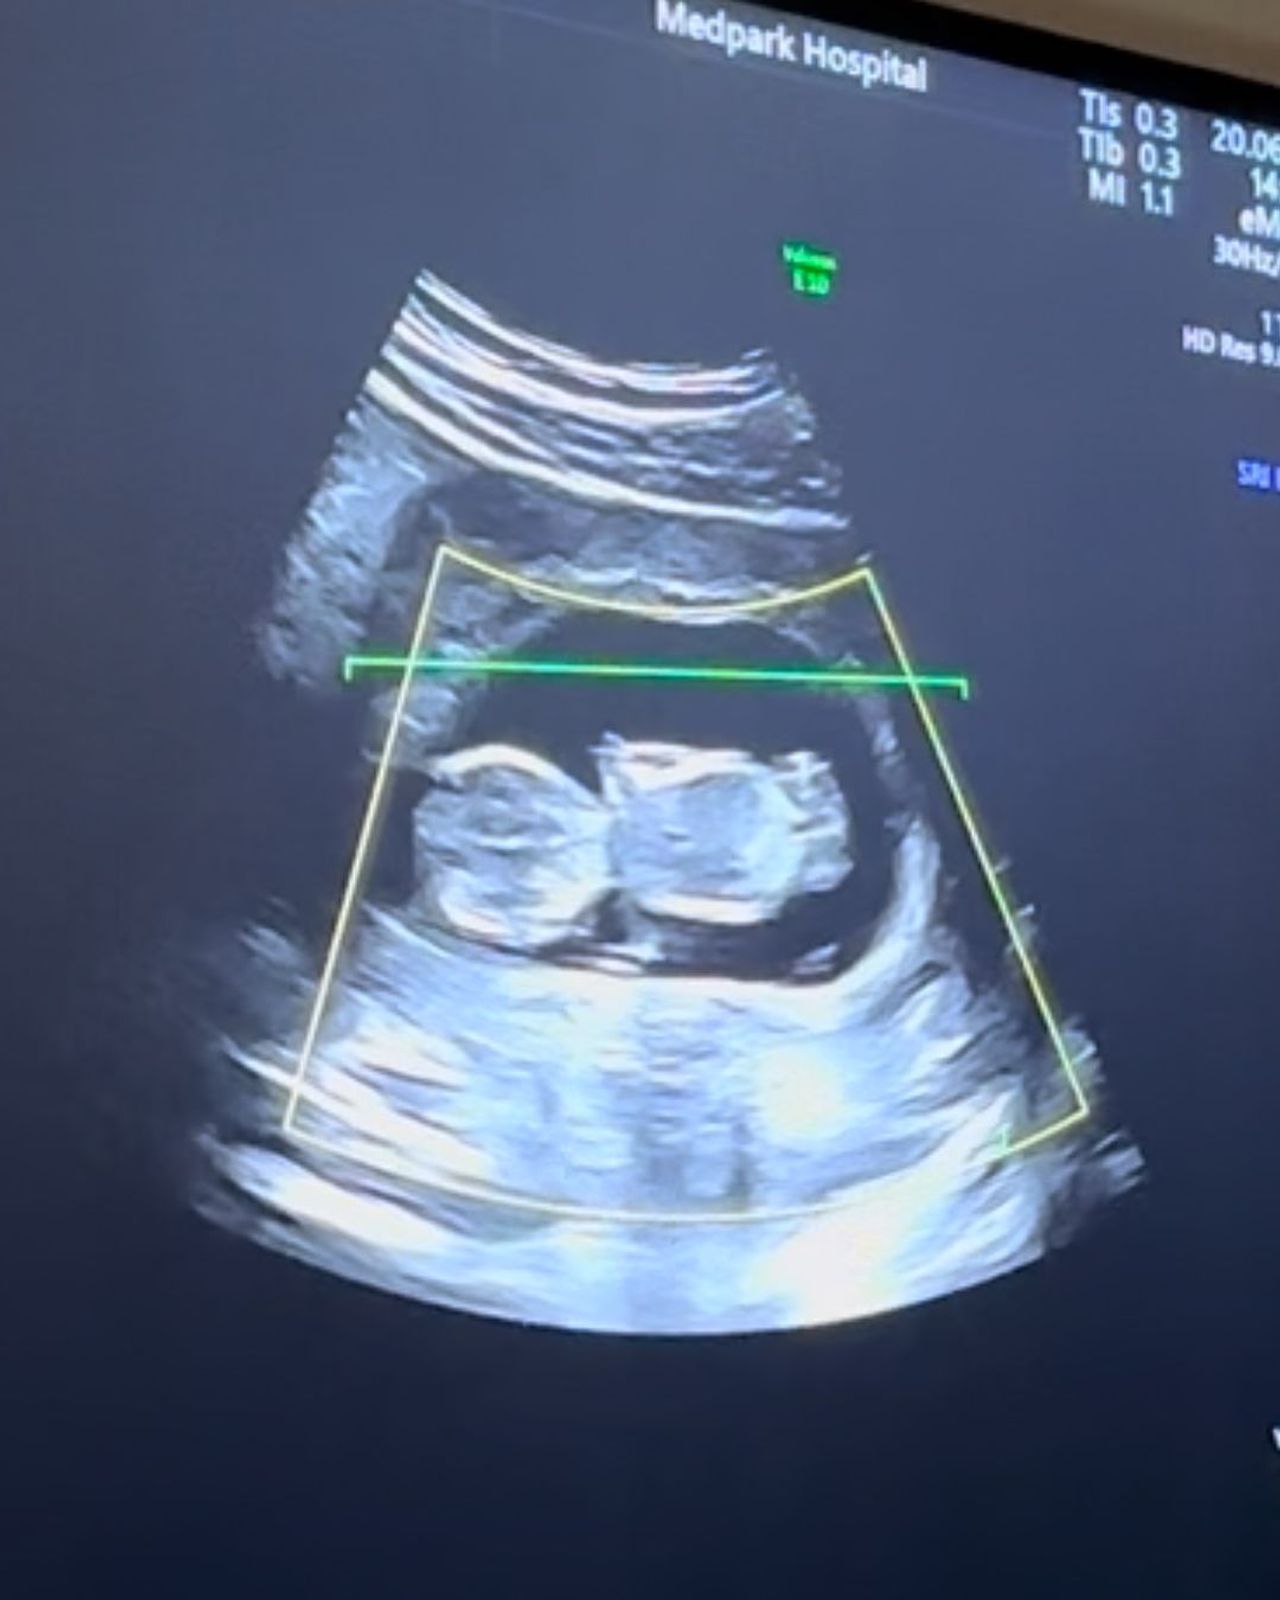

หลังจากที่นักร้องสาว แพท วง KLEAR แต่งงานและใช้ชีวิตคู่กับสามีหนุ่มสถาปนิกมาเกือบปี ในที่สุดทั้งคู่ก็มีข่าวดีให้ครอบครัว เพื่อนๆ แฟนๆ ได้เฮกัน ด้วยการประกาศว่า กำลังตั้งท้องลูกคนแรกได้ 3 เดือนแล้ว

โดยแพทได้ประกาศข่าวดีดังกล่าวด้วยการโพสต์รูปสามีกำลังจุ๊บท้องและเขียนข้อความว่า "And then there were three... จากสองเราเป็นสามเราแล้วนะ @shif.samascha #13weekspregnant"